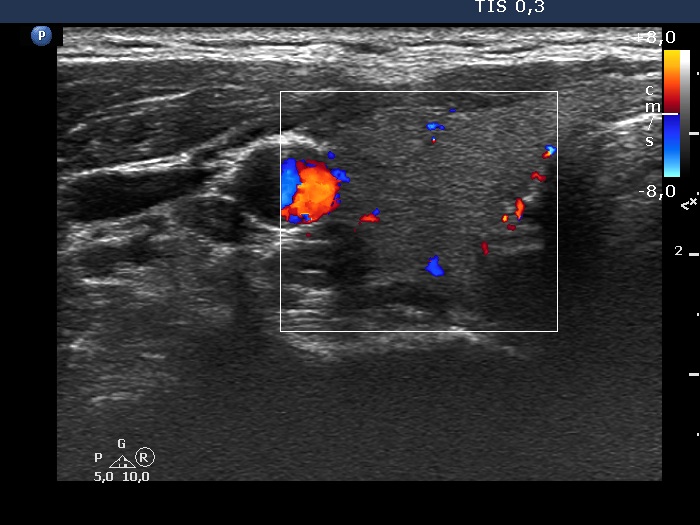

Two years after the first visit (second row of images):

Clinical presentation: The patient requested evaluation of neck complaints. Her left thyroid became painful and she became feverish 3 weeks ago. She suffered from upper airways infection 2.5 months before the onset of complaints.

Palpation: Both lobes became hard. The right lobe was very sensitive while the left was painful on palpation.

Laboratory tests: TSH 0.02 mIU/L, FT4 30.7 pM/L, CRP 51.8 mg/L.

Ultrasonography: The thyroid became minimally hypoechoic and more hypoechoic areas have appeared in both lobes. The echogenicity index was 20% and 50%, right and left lobe, respectively. The vascularity was decreased.

Suggestion. Steroid therapy.